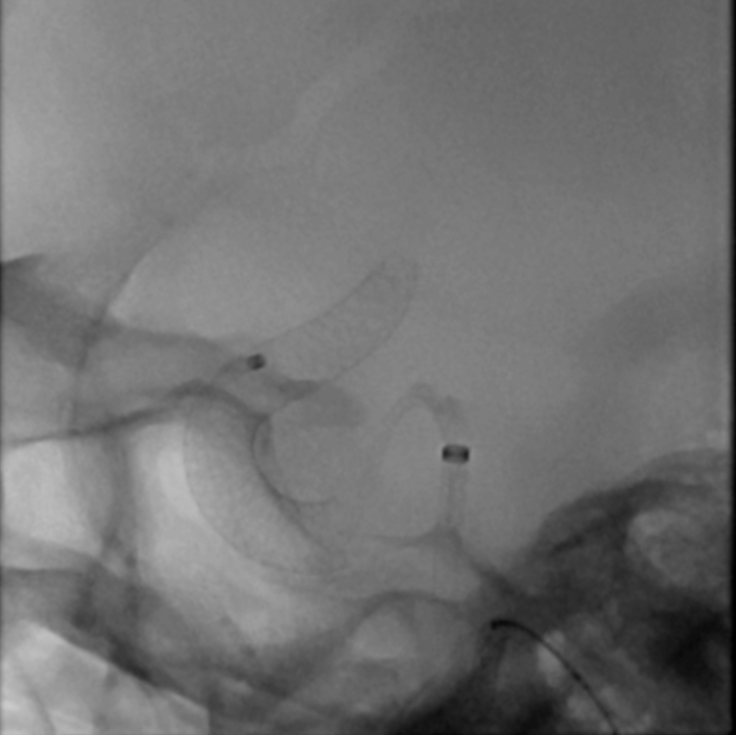

在做好了充足的术前准备后,我科介入治疗团队给黄女士进行了密网支架置入术。

手术过程

支架导管到位后,缓慢释放血流导向密网支架。